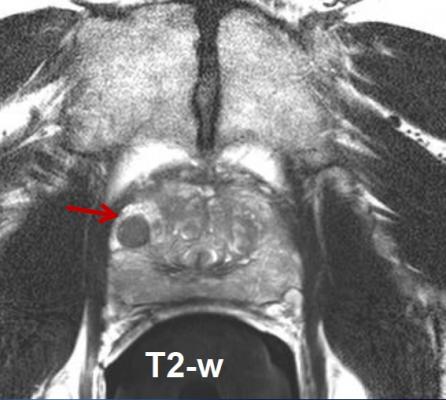

“Prostate cancer remains the sole malignancy where treatment is always delivered to the whole organ in routine practice,” said Mitchell Machtay, M.D., chairman of the Department of Radiation Oncology at UH Case Medical Center and Case Western Reserve University School of Medicine, and principal investigator of the new study. “It is time to investigate new and better options for low-risk prostate cancer patients. Radiology advancements in ultrasound, CT [computed tomography] and MRI [magnetic resonance imaging] enable us to accurately identify, measure and target malignancies more precisely than ever before.”